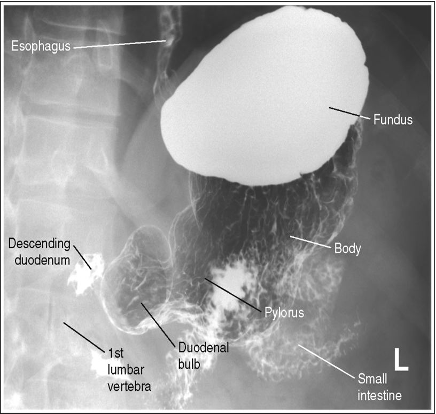

What position is this patient in?

RAO (Patient is PA due to air in fundus, but the spine is rotated so this is an RAO)